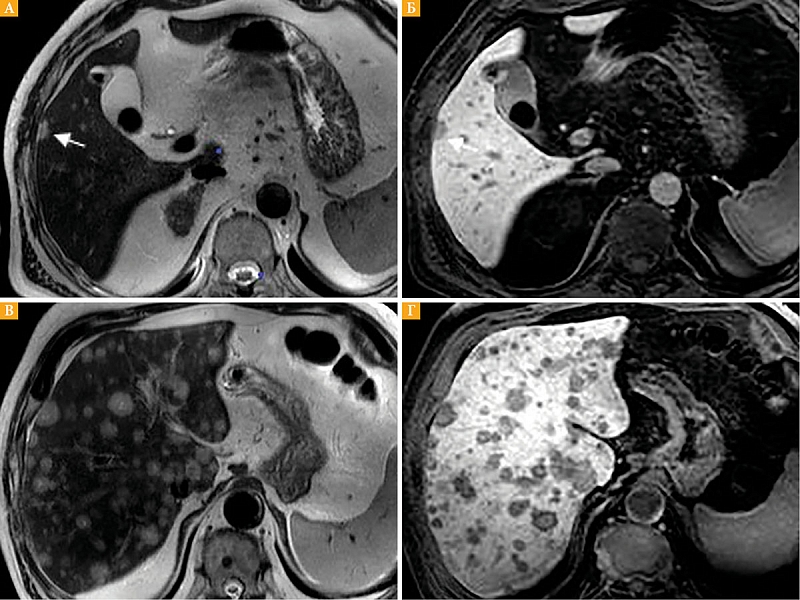

Рис. 1. Метастазы увеальной меланомы в печень: А (на Т2-ВИ) и Б (Т1-ВИ) с контрастным усилением, гепатобилиарная фаза – визуализируется единичный очаг в правой доле печени (стрелка); В (Т2-ВИ) и Г (Т1-ВИ) с контрастным усилением

Размеры очагов варьировали от 2 до 78 мм (средний размер очага 4,5 мм). Единичные очаги (до 4 мм) выявлены у четырех пациентов (рис. 1А, 1Б), множественные очаги – у семи (рис. 1В, 1Г). Множественные очаги визуализировались в обеих долях печени, единичные – в правой доле.

При нетипичных для метастазов характеристиках выполнение гепатоспецифической фазы позволило дать более точное представление о природе подозрительных очагов. Отсутствие накопления контрастного вещества в отсроченную фазу в подозрительных очагах свидетельствует об отсутствии в них гепатоцитов (рис. 1).